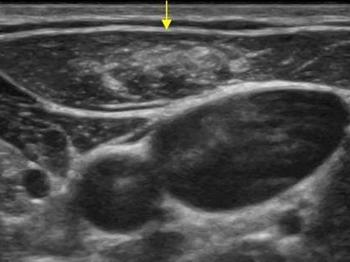

Lenf bezleri doğuştan vücudumuzda bulunan ve vücudumuzun mikroplara karşı ilk koruyucu tabakalarıdır. Enfeksiyon ajanları ile karşılaşınca büyürler, enfeksiyon tedavi edilince ya da vücut tarafından etkisiz hale getirilince küçülürler. Ayrıca lenf bezleri bir takım hematolojik kan hastalıkları (lenfoma, lösemi vb.) ve bazı kanserlerde de etkilenirler ve büyürler. Büyümüş bir lenf bezinin enfeksiyona mı yoksa kansere mi bağlı olduğunu anlamakta ultrasonu çok önemli bilgiler vermektedir. Buna göre de hastanın takip, medikal tedavi ve biyopsi kararı verilmektedir.